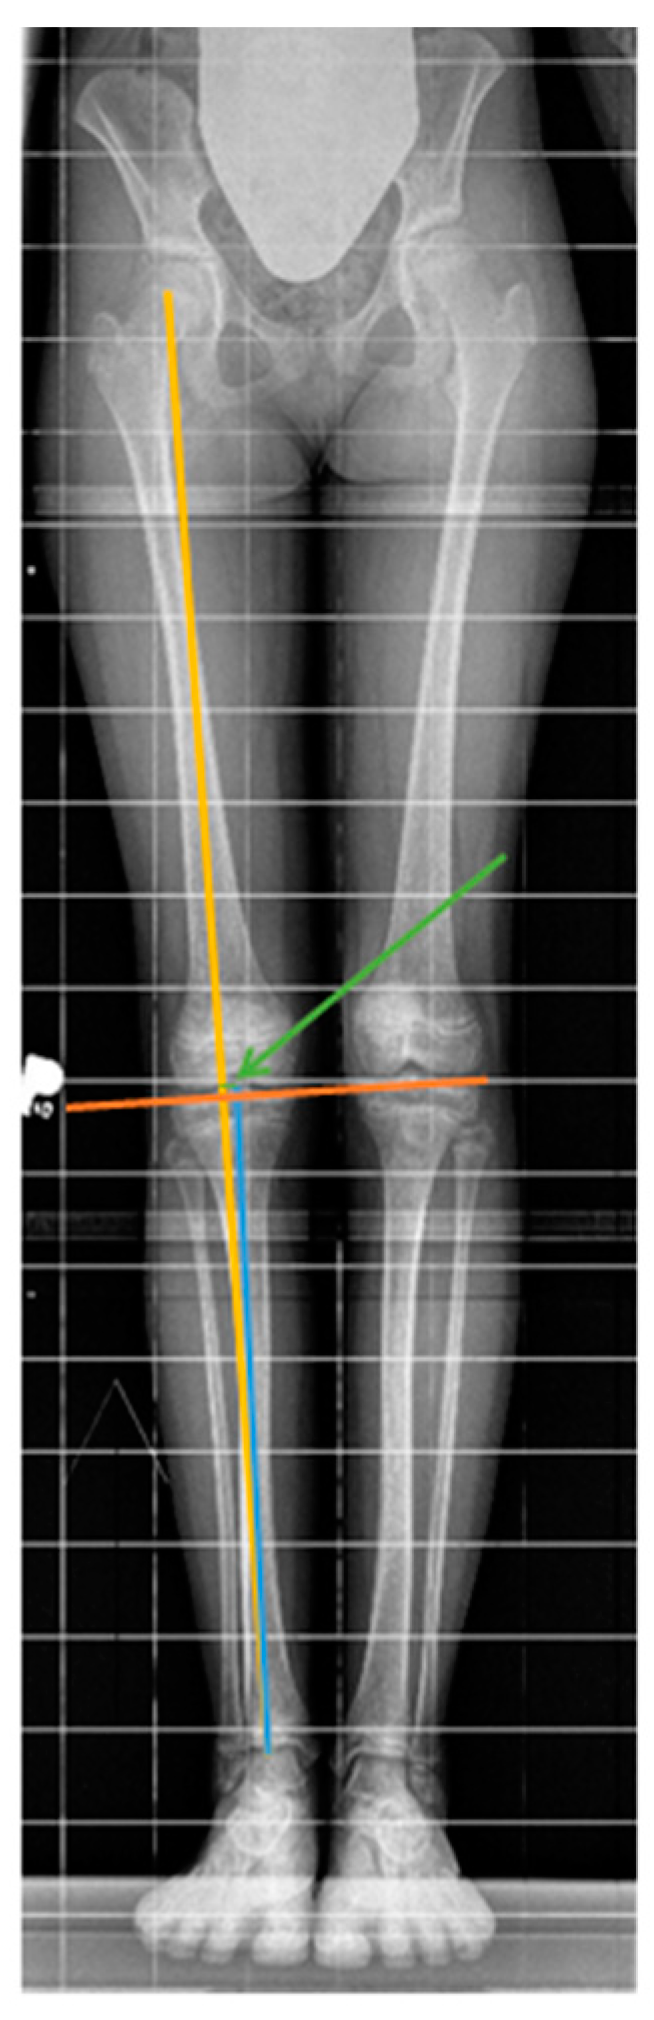

Limb Axis Disorder During Leg Length Discrepancy Treatment with Temporary Epiphysiodesis Using Eight-Plate Implants

2.2. Investigated Parameters